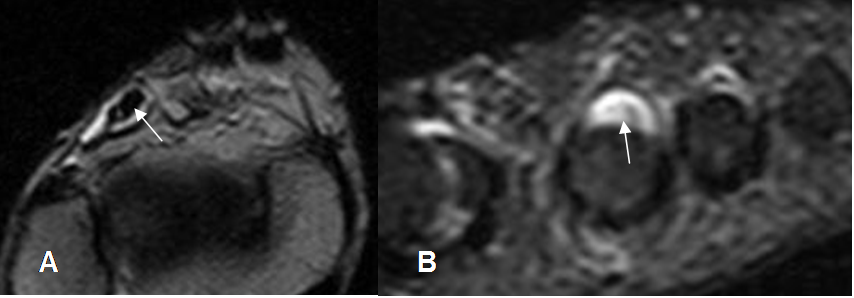

Fig 73. Tenosinovitis de músculos anteriores.

A: RM axial T2 del tobillo y B: RM coronal del pie en STIR. Líquido rodeando completamente

el tendón del extensor largo de los dedos y extensor propio del 2º dedo.